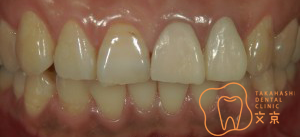

■前歯を治したい。 オールセラミックスによる審美治療

■前歯を治したい。40代男性 オールセラミックスによる審美治療

■前歯を治したい 精密審美治療・セラミックス治療

■前歯 精密審美治療

■前歯のセラミックス治療 審美治療

■前歯のオールセラミックス治療

■保険の前歯を直したい